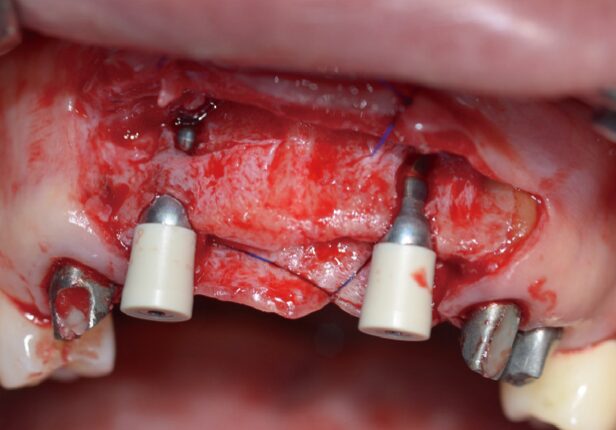

Colocação do implante

caso de estudo

Posicionamento AXA